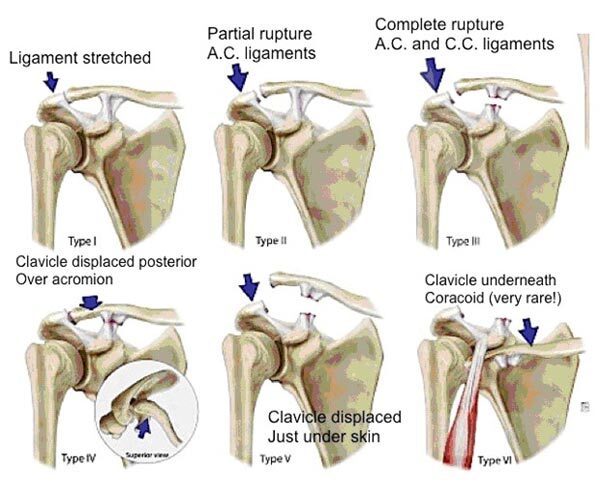

AC joint injury classification scheme

Type I injuries involve purely an AC joint sprain with intact CC ligaments. Type II injuries involve complete tearing of the AC joint and a sprain of the CC ligament with the CC measurement being < 25% greater than of the contralateral shoulder. Type III, IV, V, and VI injuries all involve complete tearing of both the AC and CC ligaments. Type III injuries have a CC distance measurement between 25 and 100% greater than that of the contralateral side (this patient) compared to Type V injuries which have a CC distance > 100% of the contralateral side. Type IV and VI injuries represent posterior and inferior dislocation of the clavicle, respectively. The coracoacromial ligament is generally spared in these injuries